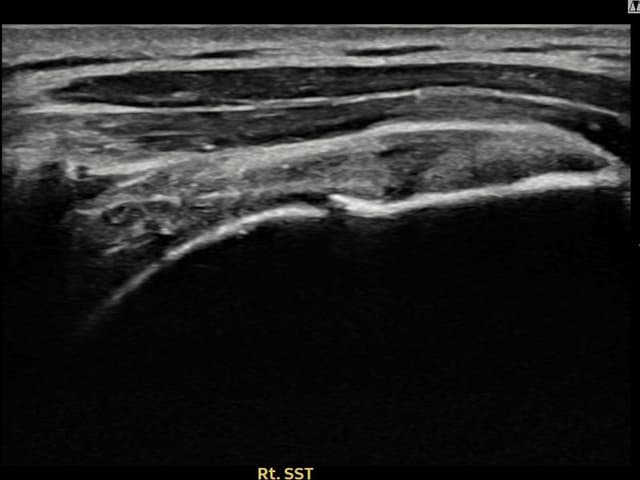

[촬영시기:22.08.10]

[석회분쇄흡입술] 우측 어깨 극심한 야간 통증으로 수면이 불가능해진 50대 여성 환자로, X-ray에서 우측 극상근건 내 석회 침착이 확인되어 석회분쇄흡입술을 시행하였습니다.